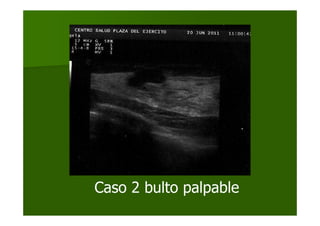

Caso 2 bulto palpable